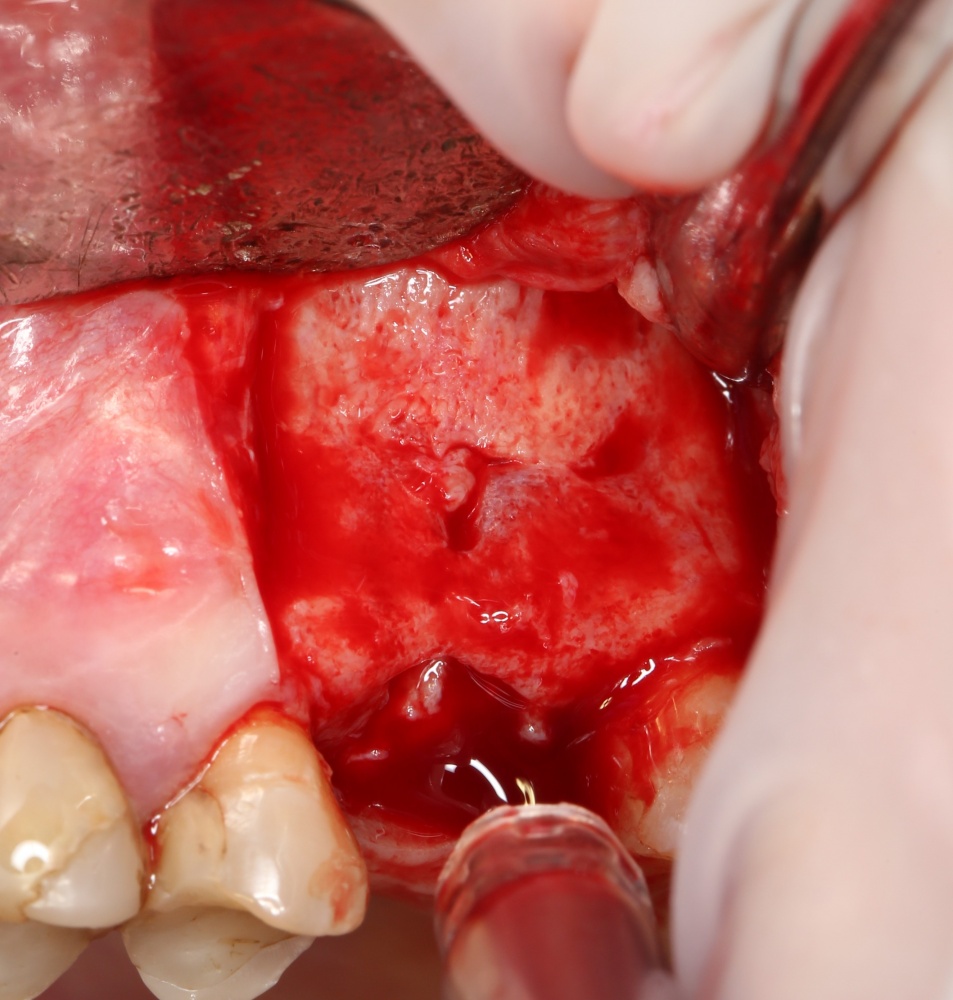

Простой синуслифтинг. Часть I.